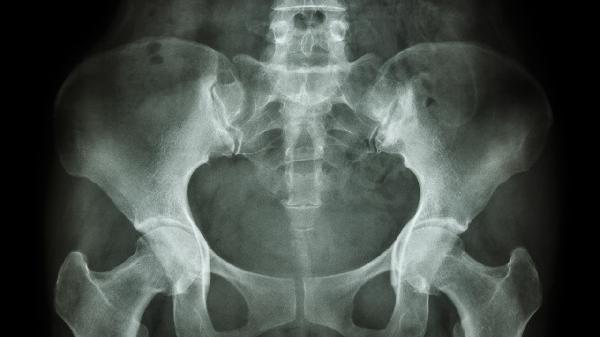

4、髂骨位置对比

双手拇指按压髂前上棘与耻骨联合形成三角形,正常应呈垂直平面。若耻骨联合明显低于髂前上棘连线,或站立时小腹前凸伴随臀部后移,可判断为骨盆前倾。该方法需在放松状态下测量,女性需排除妊娠期生理性骨盆变化。